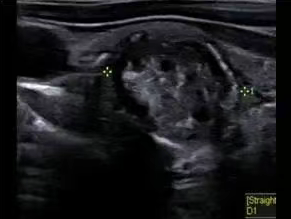

(3)纵切图像及彩色多普勒图像 二、(1)位患者结节的横向图像:有边缘样但不连续的钙化

(2)结节的纵向图像

考虑良性还是恶性,是否需要进行活检?结果可能如何?你怎么认为? 简单分析下: 形:片状或地图样低回声,边界模糊 位:单侧或局部,其余实质回声正常 血:血流不增多,偶见稀疏点状